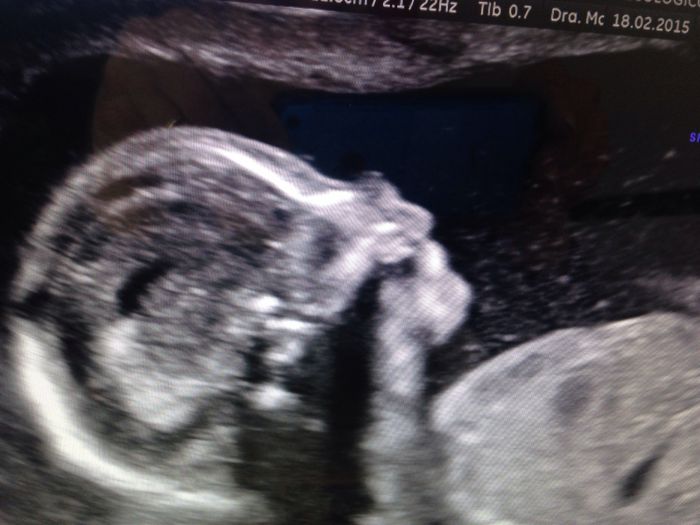

Já mám kontrolu zitra u mojí dr.a v pondělí v prenatalu velký UZ.už se těším!!!a chci si nechat potvrdit pohlaví,tak jsem zvědavá,jestli je to pořád kluk nebo uvidí holčičku